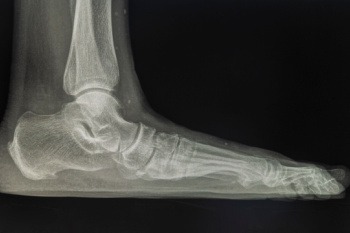

To figure out the cause of foot pain, podiatrists utilize several different methods. This can range from simple visual inspections and sensation tests to X-rays and MRI scans. Prior medical history, family medical history, and any recent physical traumatic events will all be taken into consideration for a proper diagnosis.

Due to the wide variety of potential causes of ankle pain, podiatrists will utilize a number of different methods to properly diagnose ankle pain. This can include asking for personal and family medical histories and of any recent injuries. Further diagnosis may include sensation tests, a physical examination, and potentially x-rays or other imaging tests.